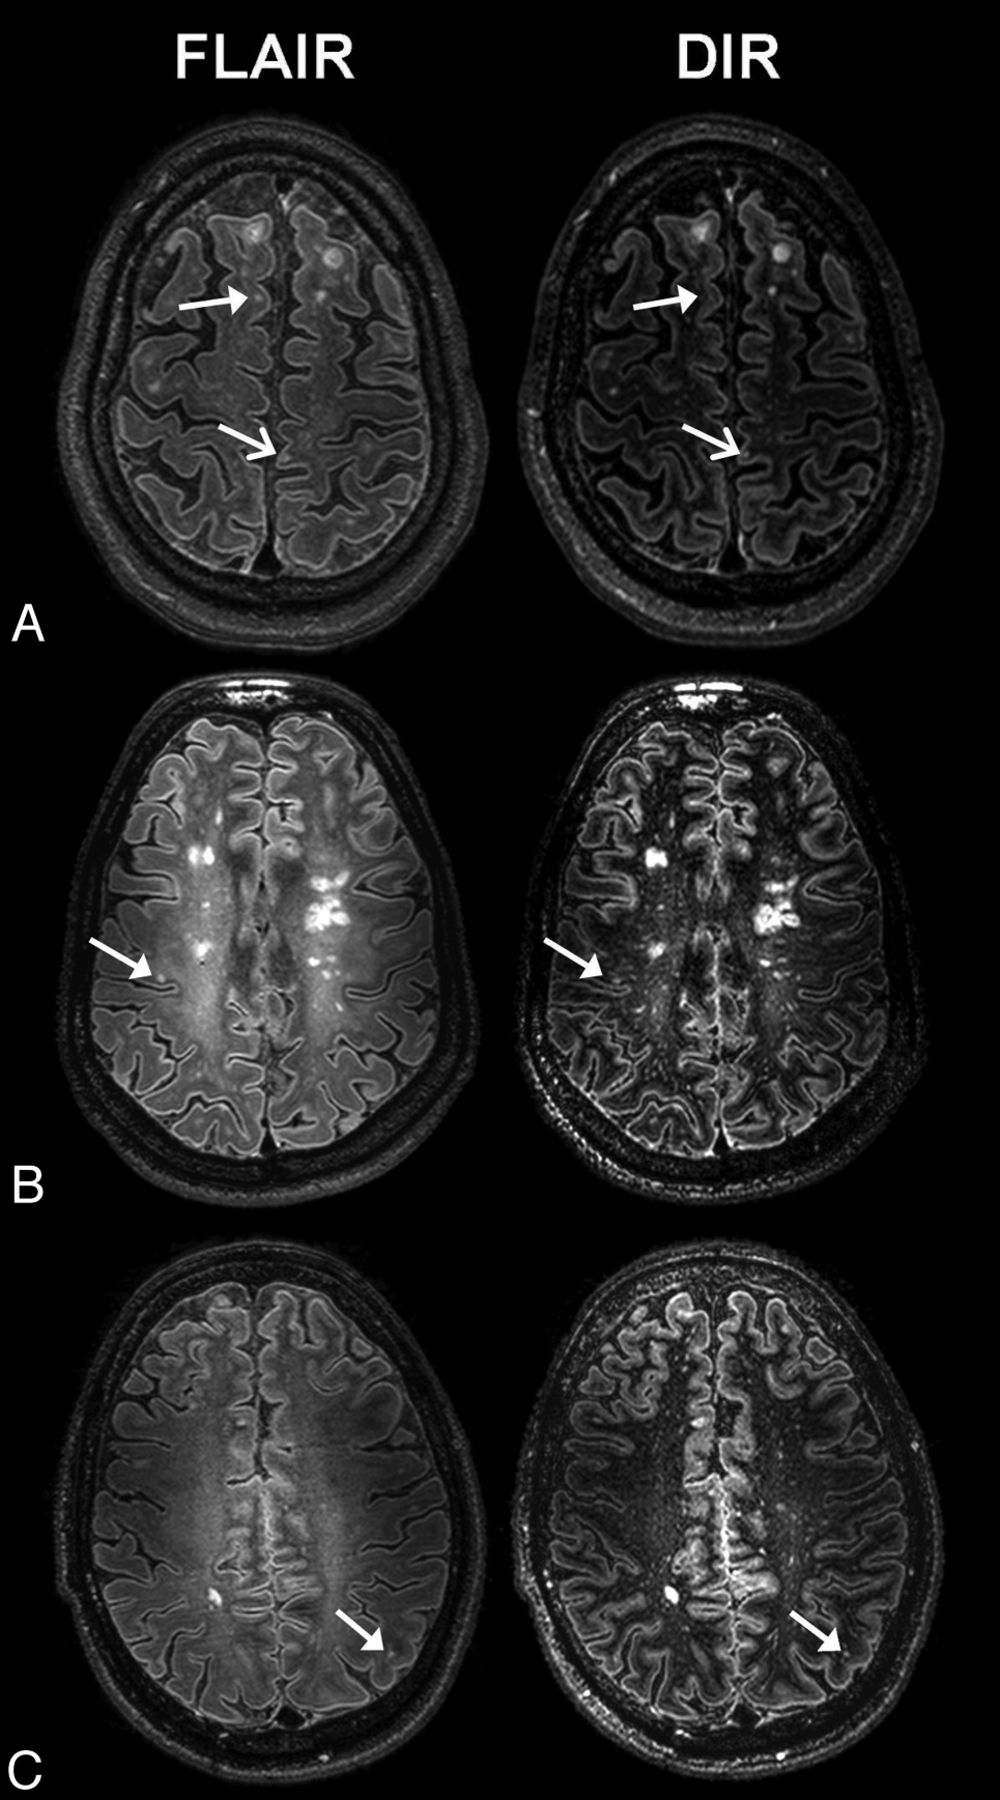

Overall, the 3D-FLAIR sequence detected the highest number of lesions compared with other sequences. In total GM, 217 lesions were detected at 3D-FLAIR, which was 89% more compared with 3D-DIR (115), 87% more compared with 2D-T2WI (116), and 224% more compared with 3D-T1WI (67). The difference was the largest for the detection of mixed lesions at 3D-FLAIR (178), with which 147% more mixed lesions were detected than on 3D-DIR (72), 117% (82) more than on 2D-T2WI, and 242% (52) more than on 3D-T1WI. The highest number of purely intracortical lesions was detected at 3D-DIR (43), a 10% increase compared with 3D-FLAIR (39) and a 27% and a 187% increase when compared with 2D-T2WI (34) and 3D-T1WI (15), respectively. Images of intracortical lesion detection with the different 7T sequences used in the study are shown in Fig 2.

Axial 3D-DIR, 3D-FLAIR, 3D-T1WI, and 2D-T2WI at 7T MR imaging of a 37-year-old female patient with secondary-progressive MS. Arrows indicate an intracortical lesion that was scored on 3D-FLAIR and 2D-T2WI but not on 3D-DIR and 3D-T1WI.